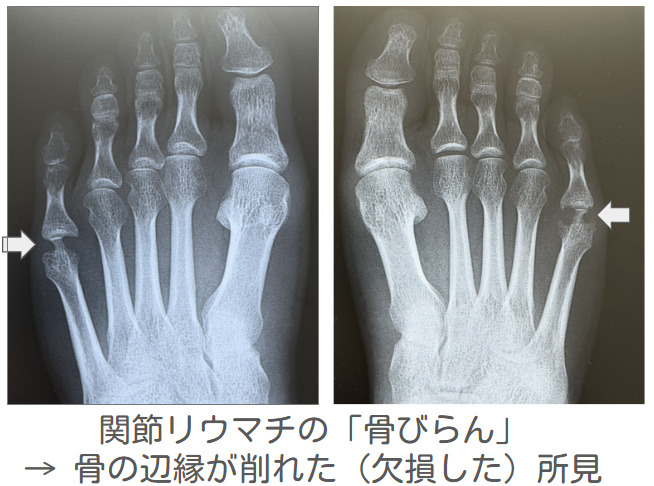

画像検査では、X線で関節破壊の有無を評価しますが、早期には変化が乏しいこともあります。そのため、関節エコーやMRIを用いて、滑膜炎や骨病変を早期に捉えることがあります。これらを踏まえ、2010年ACR/EULAR分類基準などを参考に診断します。